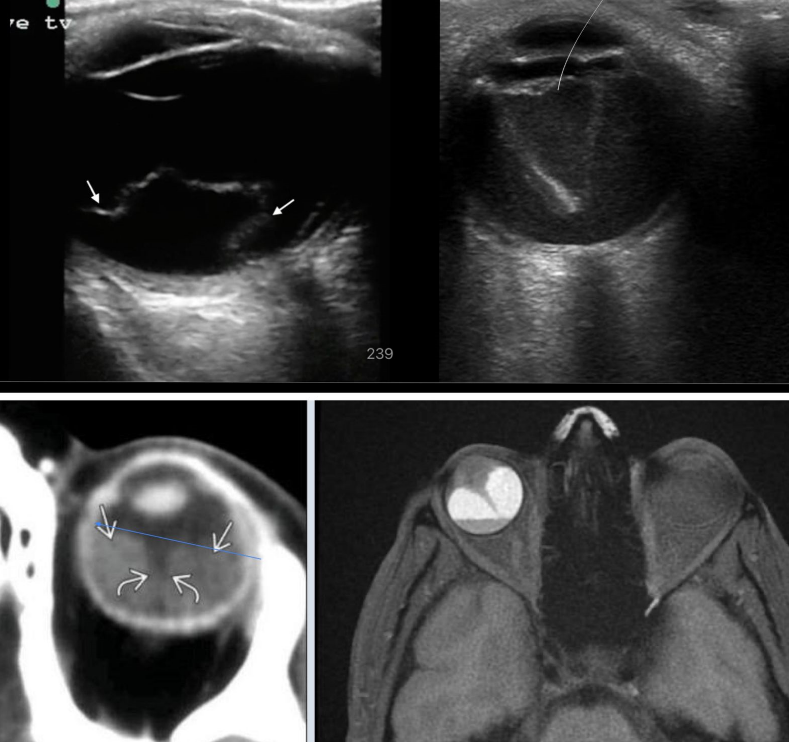

Desprendimiento de retina

• Regmatógeno: traumatismo

• No regmatógeno: exudativo → neoplasia | traccional → retinopatia diabetica

9

estudios de imagen desprendimiento de retina

• USG: retna doblada y brillante, forma triangular

• TC y RM: retina triangular, hiperdensidad